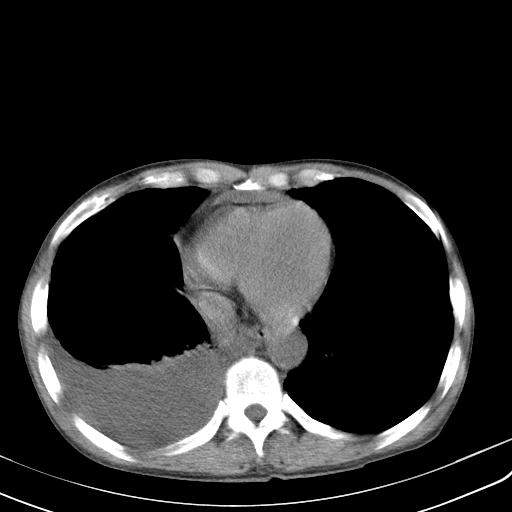

男性 75  咳嗽 一周前发热最高达39

右肺继发型tb并右侧tb性胸腔炎,右侧胸腔大量积液并右下肺膨胀不全,慢支肺气肿、多发肺大泡。建议抽胸水实验室检查并复查排除恶性在占位。

右上肺继发型肺结核,右胸腔中等量积液。

结核的基础上有纵隔淋巴结肿大,右侧有胸水,但右侧纵隔反而窄,说明有肺有不张。

再就是右下肺有块影,和不张混合,还是不能除外肺癌。

补充材料,患者2月份ct片大致正常,双侧胸腔积液,2月份抽胸水未发现ca细胞,现患者发热,痰多,各气管通畅,

1)右肺继发型肺结核。2)左肺胸膜下多发性肺大泡。3)右侧胸腔积液。